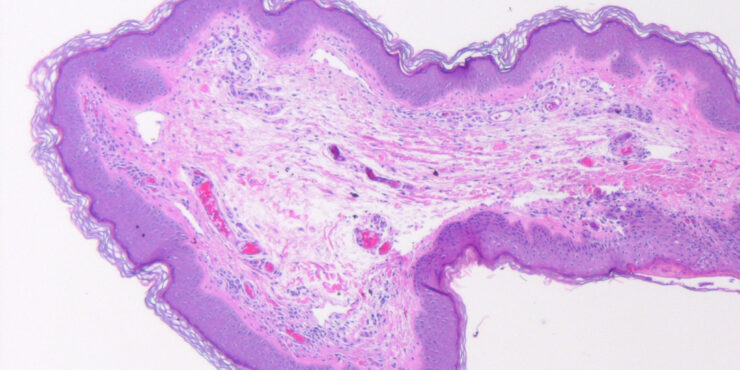

Read MoreFibrous papule (angiofibroma) = حطاطة تليفية =ليفوم وعائي OLYMPUS DIGITAL CAMERA OLYMPUS DIGITAL CAMERA FIBROUS PAPULE Currently, there is some disagreement as to whether fibrous papule represents a neoplastic process or a hamartoma.Fibrous papule (perifollicular fibroma) presents mainly as a solitary papule or as several dome-shaped, skin-colored, pigmented, or reddish lesions situated on the face, […]